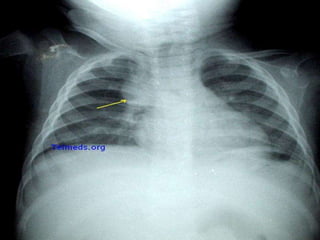

CLINICA [5]

Enfermedad de las arterias coronarias.

 La oclusión de una arteria coronaria produce una inadecuada oxigenación

de un área del miocardio y muerte celular (Infarto del miocardio).

 La severidad del cuadro depende del tamaño y localización de la arteria

envuelta y si el bloqueo es completo o no.

 Los bloques parciales producen angina durante o después del ejercicio.

 Se tratan con angioplastia coronaria y con los puentes o by-pass de las

arterias coronarias.